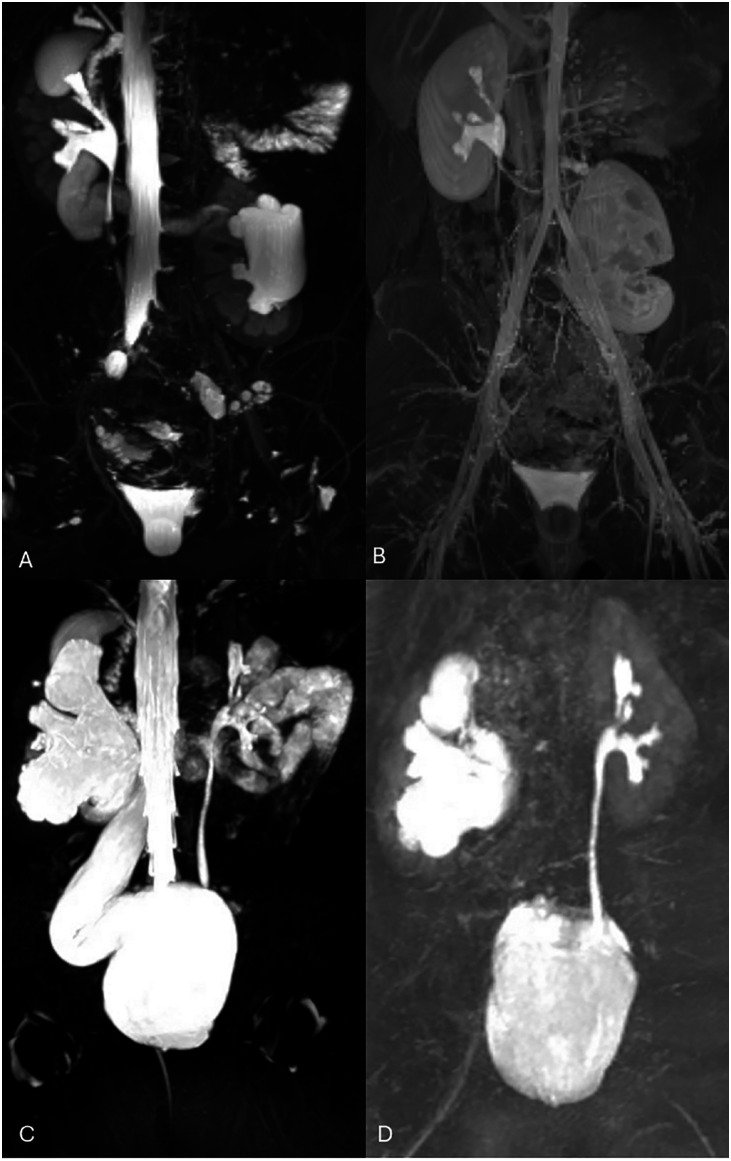

磁共振尿路造影(MRU)已经成为儿科泌尿外科的一种强大的成像方式,在不暴露于电离辐射的情况下提供全面的泌尿道解剖和功能评估。本文对MRU的技术、临床应用、优势和最新进展进行了深入分析。传统的成像技术,如超声、排尿膀胱尿道造影和核显像,早已被用于评估儿童尿路异常;然而,这些方法在解剖分辨率和功能评估方面存在固有的局限性。MRU结合了高分辨率解剖成像和动态功能分析,使其在评估肾积水、肾盂输尿管连接处阻塞和输尿管异位等情况时特别有价值。MRU技术的进步,包括使用3T MRI进行优越的空间分辨率、扩散加权成像和动态对比度增强成像,增强了其诊断能力。评估肾脏转运时间和鉴别肾功能的能力可以精确评估梗阻性尿路病变和先天性异常。尽管在年幼的儿童中需要镇静和较长的获取时间,但与传统成像相比,MRU显示出更高的准确性,减少了多次诊断研究的需要。实时MRI、快速成像技术和基于人工智能的重建技术的最新发展进一步优化了MRU的效率和诊断效用。随着MRU的不断发展,其在儿科泌尿外科的作用有望扩大,在某些情况下可能取代传统的成像方式。这篇综述强调了MRU在儿童尿路评估中的日益重要的意义,强调了其改善临床决策和患者预后的潜力。

Magnetic Resonance Urography (MRU) has emerged as a powerful imaging modality in pediatric urology, offering comprehensive anatomical and functional assessment of the urinary tract without exposure to ionizing radiation. This review provides an in-depth analysis of MRU's technical aspects, clinical applications, advantages, and recent advancements. Traditional imaging techniques, such as ultrasound, voiding cystourethrography, and nuclear scintigraphy, have long been utilized for evaluating pediatric urinary tract anomalies; however, these methods have inherent limitations in anatomical resolution and functional assessment. MRU combines high-resolution anatomical imaging with dynamic functional analysis, making it particularly valuable in evaluating conditions such as hydronephrosis, ureteropelvic junction obstruction, and ectopic ureters. Advancements in MRU technology, including the use of 3T MRI for superior spatial resolution, diffusion-weighted imaging, and dynamic contrast-enhanced imaging, have enhanced its diagnostic capabilities. The ability to assess renal transit times and differential renal function allows for precise evaluation of obstructive uropathies and congenital anomalies. Despite requiring sedation in younger children and longer acquisition times, MRU has demonstrated superior accuracy compared to conventional imaging, reducing the need for multiple diagnostic studies. Recent developments in real-time MRI, faster imaging techniques, and AI-based reconstructions have further optimized MRU's efficiency and diagnostic utility. As MRU continues to evolve, its role in pediatric urology is expected to expand, potentially replacing traditional imaging modalities in select cases. This review highlights the growing significance of MRU in pediatric urinary tract evaluation, emphasizing its potential to improve clinical decision-making and patient outcomes.